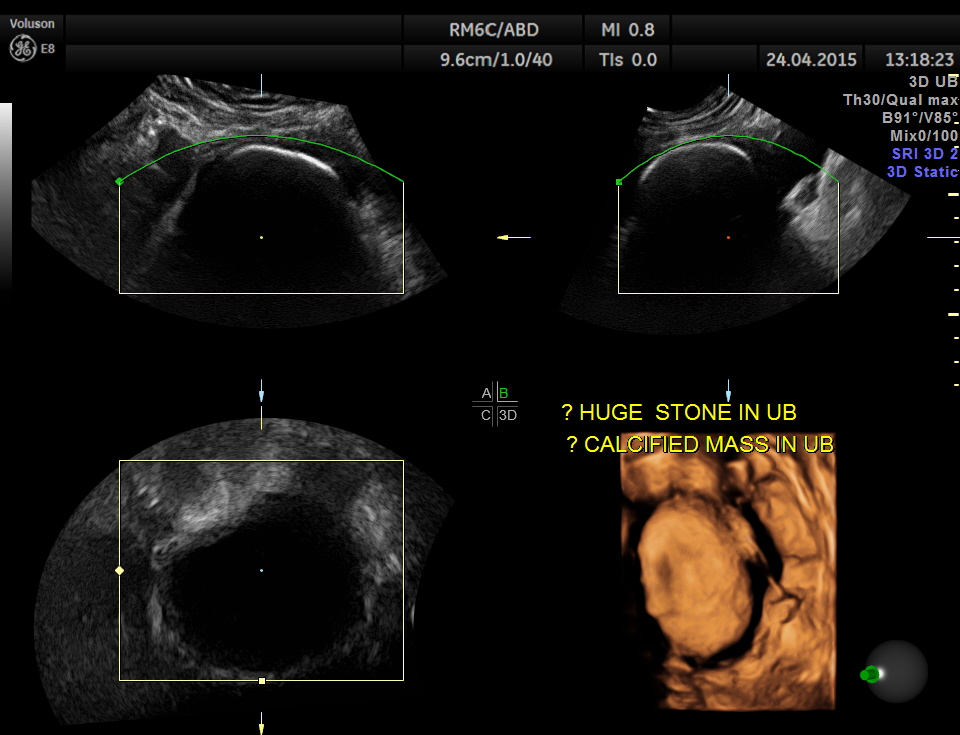

Scan of the urinary bladder in a more cephalic angle shows the following :

A large calcification in the urinary bladder – ? large urinary bladder stone , calcified median lobe of the prostate, or a calcified mass within the bladder .

3D tweaking looks more like a large stone.